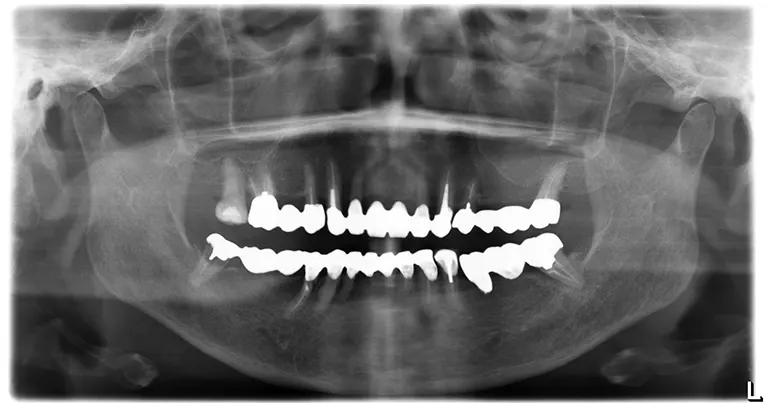

• Before インプラント治療前の状態

治療前の状態

抜歯前のレントゲン写真です。

左右下顎臼歯部はブリッジで連結されているが、動揺しているため噛むと痛みがあり

歯根破折・根菅治療の問題から抜歯を行いインプラント治療を計画としました。